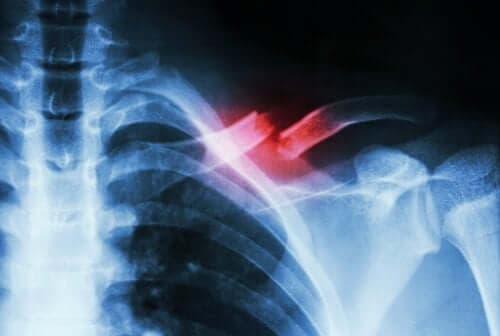

كسور الإجهاد هي كسور صغيرة الحجم تظهر لأسباب أخرى مختلفة عن التعرض للصدمات القوية. فهي إما تظهر بسبب الحركات المتحررة أو بسبب الزيادة المفاجئة في حدة أو سرعة الحركة.

من الصعب تشخيص هذا النوع من الكسور لأنها لا تظهر في الأشعة السينية. ولذلك يحتاج تشخيصها إلى طبيب متخصص وفحوصات معينة للتفرقة بينها وبين الحالات الطبية الأخرى.